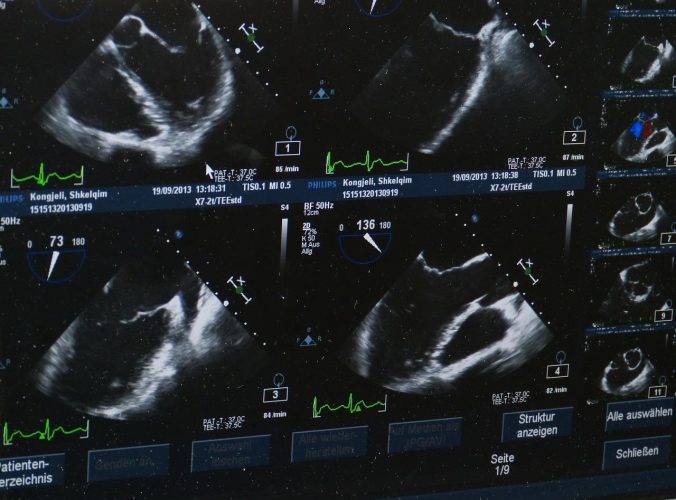

Pour surveiller le cœur

On parle d’échocardiographie. Elle sert à contrôler et à observer le sens et le débit des flux sanguins au niveau du cœur. Cet examen permet de détecter une possible atteinte des valves du muscle cardiaque, des complications ou la présence d’éventuels caillots de sang.